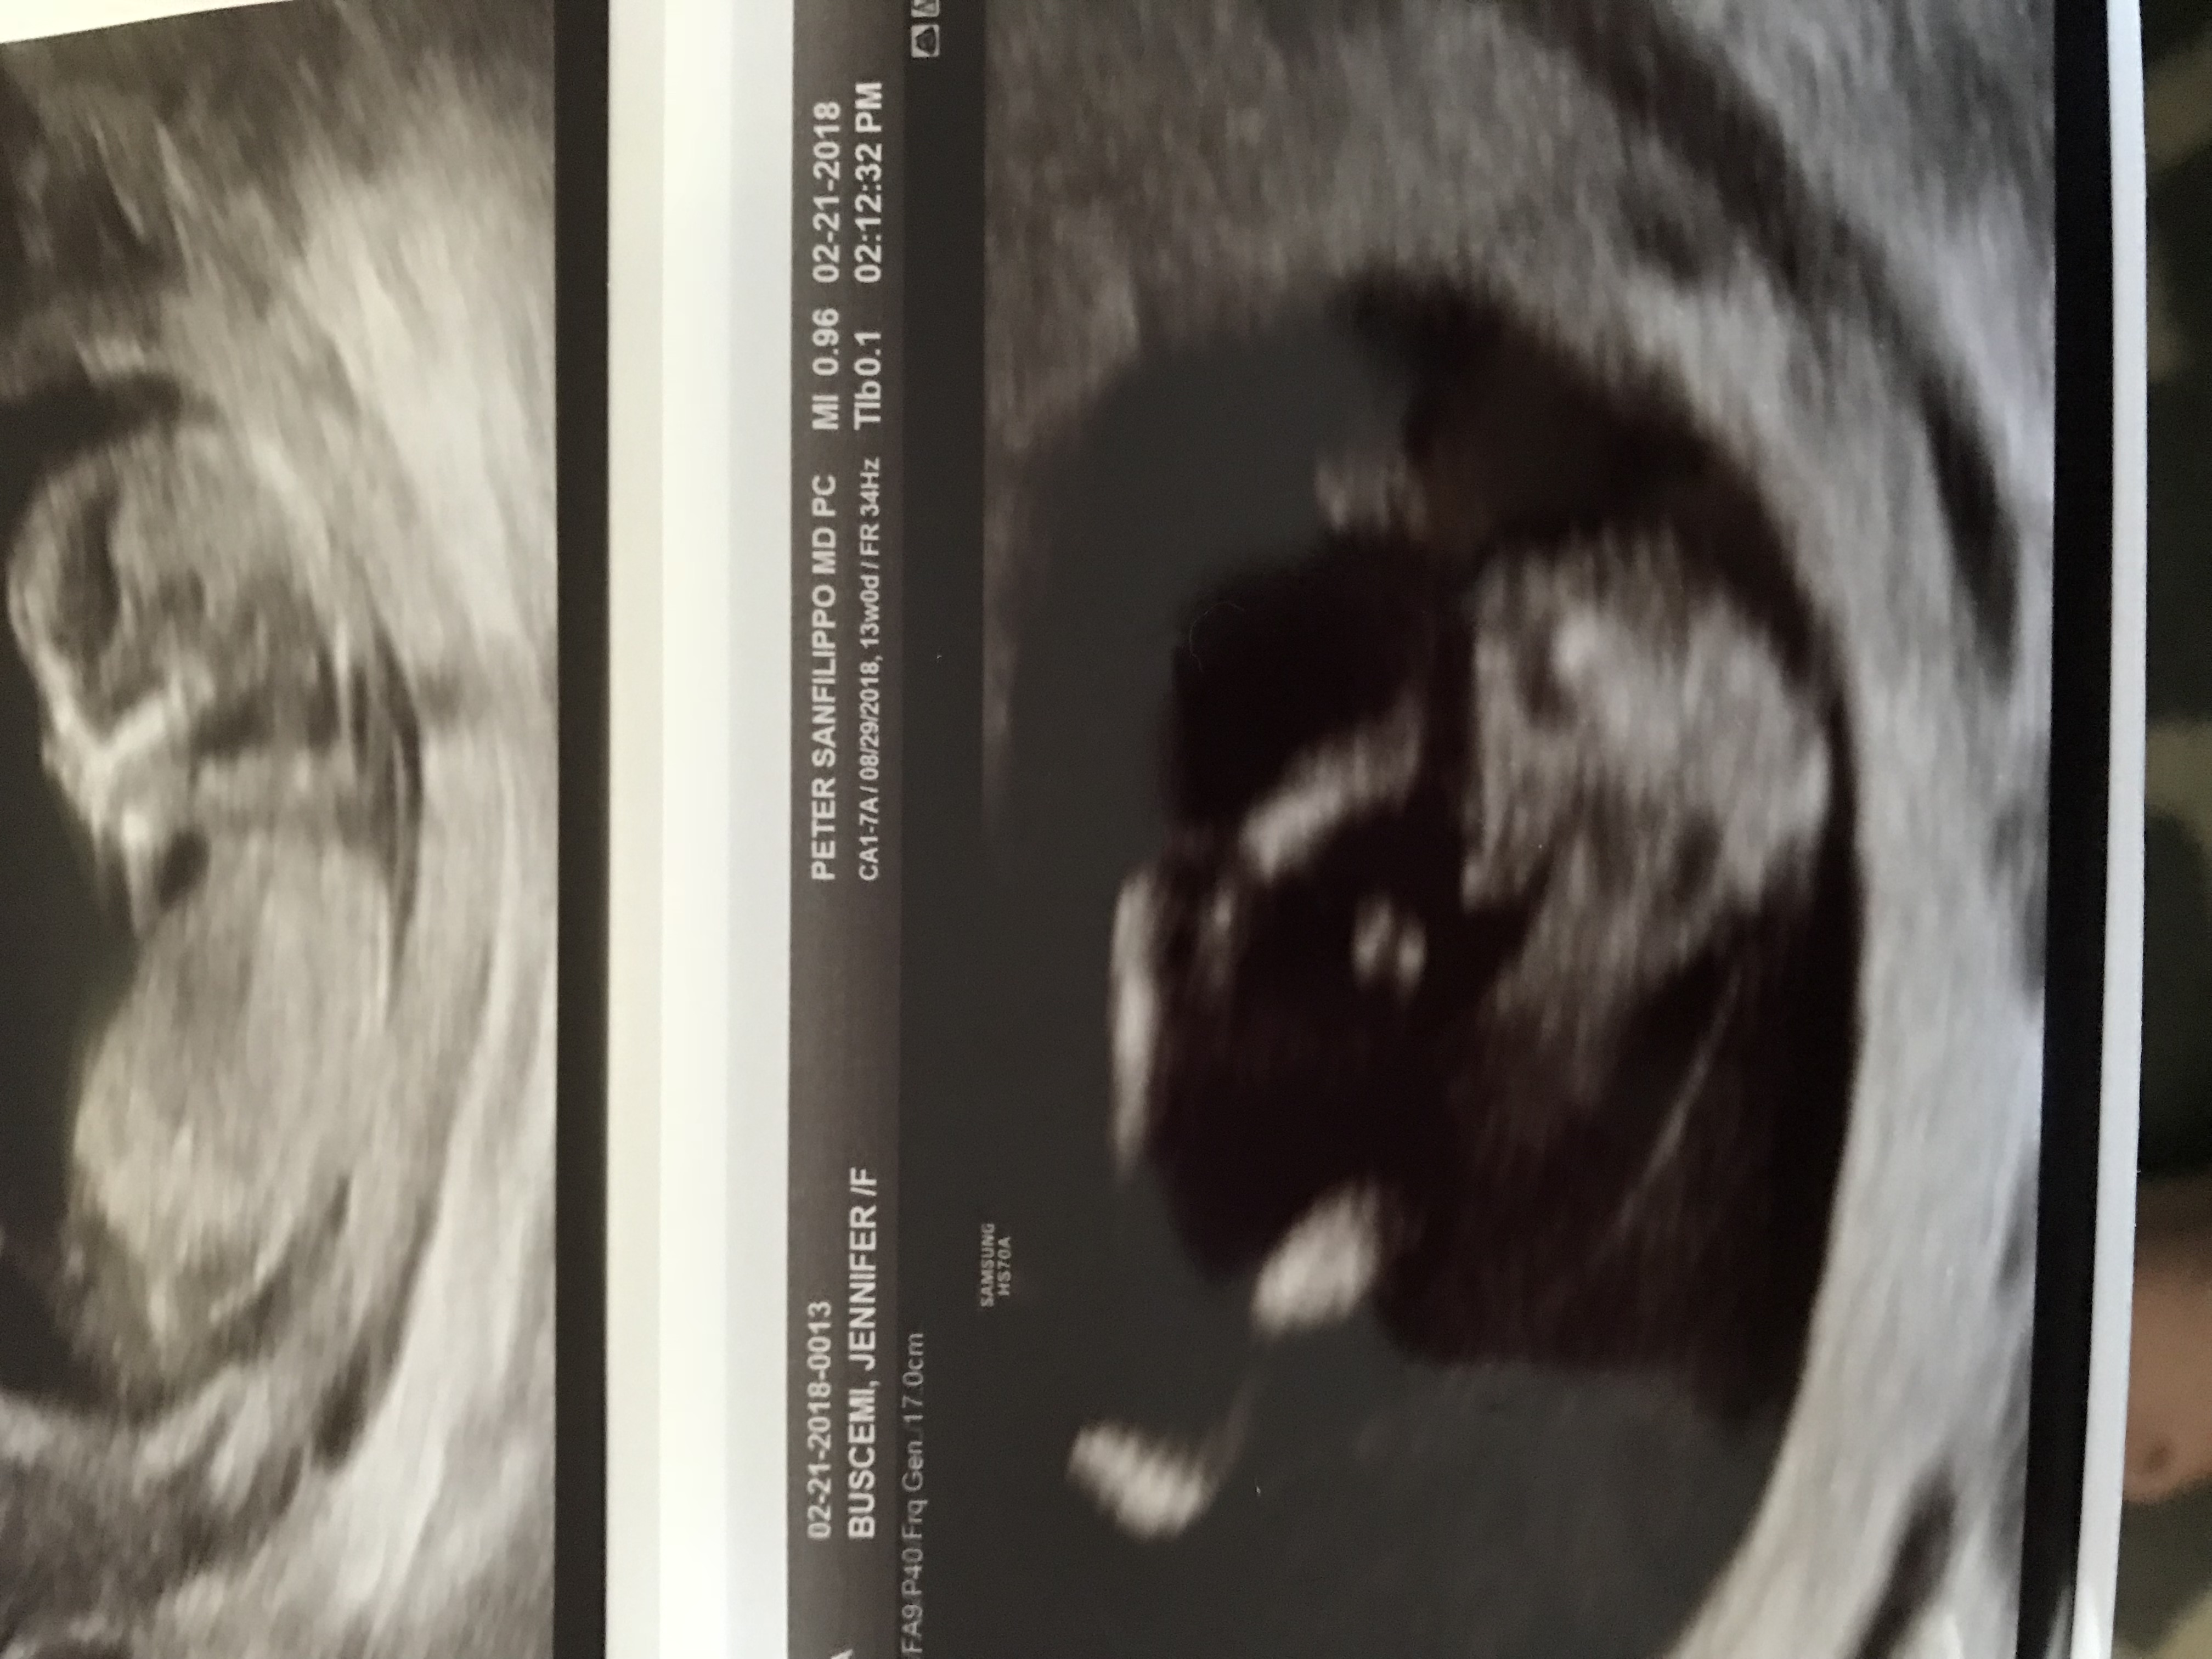

Hi everyone! Just got back from our 13 week scan and baby is perfect. Always reassuring to get pictures and hear baby’s heartbeat. The tech actually gave us her opinion on gender, which i was shocked by, since with our daughter she wouldn’t say one way or the other. Anyways, wanted to see what you guys thought. We did the NIPT test and will know 100% in the next 10 days.

Attachment 38852

Attachment 38851